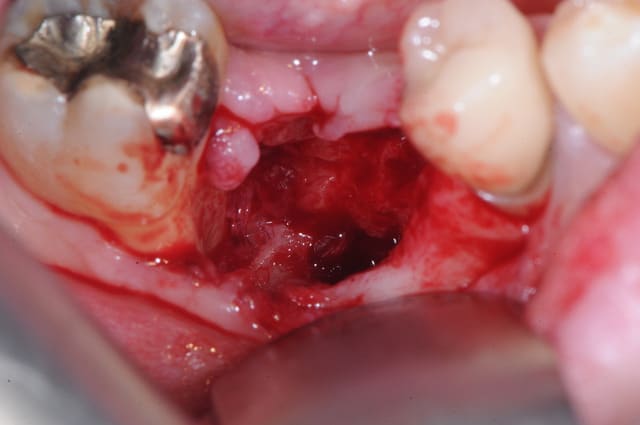

je lui ai programmé rapidement une intervention pour ce matin afin de cureter.

il a simplement fallu tirer un peu sur le séquestre